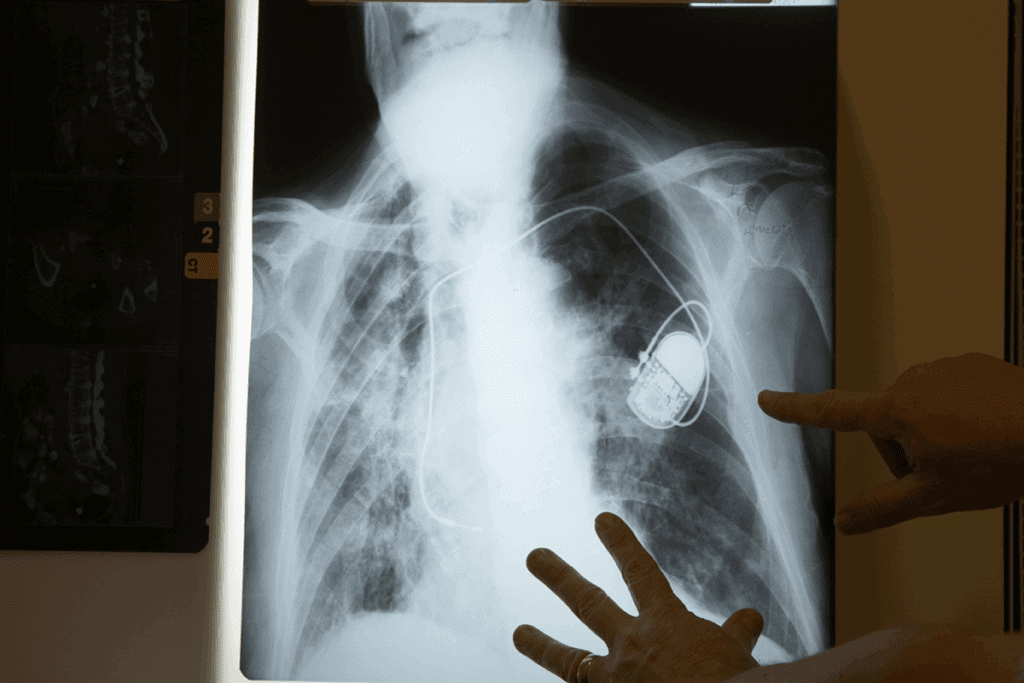

Basic Pacemaker Components and Operation

A pacemaker has two main parts: the pulse generator and the leads. The pulse generator is a small device with the battery and circuitry. It’s placed under the skin, near the collarbone. The leads are thin wires that connect the pulse generator to the heart. They send electrical impulses to keep the heartbeat regular.

When a pacemaker is put in, it’s set to meet the patient’s needs. This involves programming it to detect the heart’s rhythm and send impulses as needed.